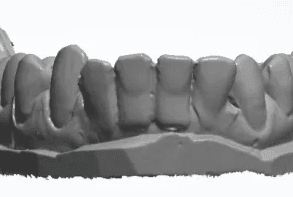

Escaneamento sem contenção

Escaneamento com contenção removida virtualmente

Quanto maior a precisão da cópia do nosso escaner maior será a acurácia da movimentação planejada.